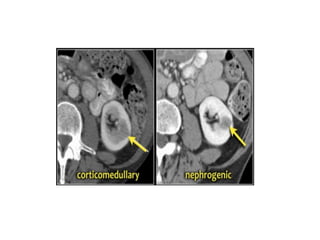

CT	thận

• Protocol

- Thì không thuốc

- Thì động mạch

- Thì vỏ tủy

- Thì thận đồ

- Thì bài tiết

Thì động mạch

• 15-25	giây sau

tiêm thuốc tương

phản.

• Khảo sát:

- Hẹp động mạch

thận

- Stent	động mạch

- Chảy máu cấp

- Bản đồ mạch máu

thận Chảy máu hoạt động/	bn

chấn thương

Thì vỏ tủy

• 25- 70	giây sau tiêm

thuốc tương phản.

- Hình thái thận

- Khối ở	thận giàu mạch

máu

- Mạch máu thận(	phình,

dị dạng,	dò)

- Tìm di	căn

Thì thận đồ

• 80-180	giây sau tiêm thuốc tương phản

- Tổn thương trong thận

- Tĩnh mạch thận,	tĩnh mạch chủ dưới

Thì bài tiết

• >	180	giây sau tiêm

thuốc tương phản

- Hệ thống bài xuất

- Khối ở	thận:	đánh giá

xâm lấn xoang,	wash

out

- Tổn thương bắt thuốc

muộn